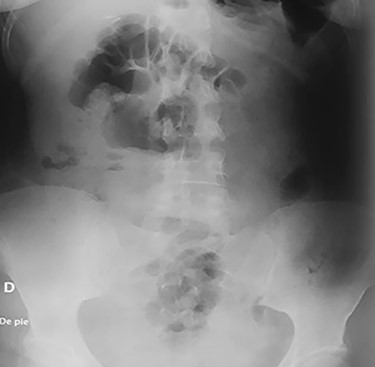

Abdominal CT, revealing two metal bodies, one in the stomach and one in the cecum.

On clinical examination, a dehydrated and tachycardic (112 bpm) patient was encountered, she had diffuse pain in her lower abdomen without tenderness. After reanimation, an abdominal X-ray found two metal bodies in the bowel (Fig. 1); therefore, a computed tomography (CT) was requested, which revealed two metal foreign bodies, (razor blades) one in the stomach and one in the cecum without pneumoperitoneum (Fig. 2). As the patient did not have any tenderness, an upper endoscopy and colonoscopy were planned. During the upper endoscopy, the razor blade was detected in the antrum and was embedded in the mucosa (Fig. 3). After several failed attempts to remove the foreign object, the procedure was interrupted due to a risk of inadvertent perforation, and surgery was decided.